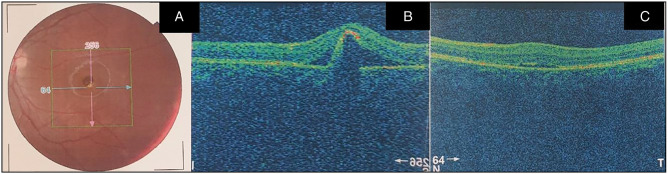

An 11-year-old boy presented to the retina outpatient clinic with a -5-year history of poor vision in the left eye. The best corrected visual acuity at presentation was 6/5 and 6/36, respectively, in the right and left eyes. Ocular examination revealed normal anterior segments in both eyes. Binocular indirect ophthalmoscopy of the right eye revealed a pink disc with a cup disc ratio (CDR) of 0.3, normal vessels while the macula had a yellowish lesion with a scrambled egg appearance and surrounding dome-shaped subretinal fluid with a flat retina and no treatable peripheral retinal lesions. The left eye had a pink disc with CDR O.3, normal vessels with a hyperpigmented lesion at the macula surrounded by a small cuff of subretinal fluid with a flat retina and no treatable peripheral retinal lesions. Optical coherence tomography scan revealed subretinal fluid in both eyes with an active choroidal neovascular membrane in the left eye. He was advised on the need for left intravitreal anti-vascular endothelial growth factor injections.